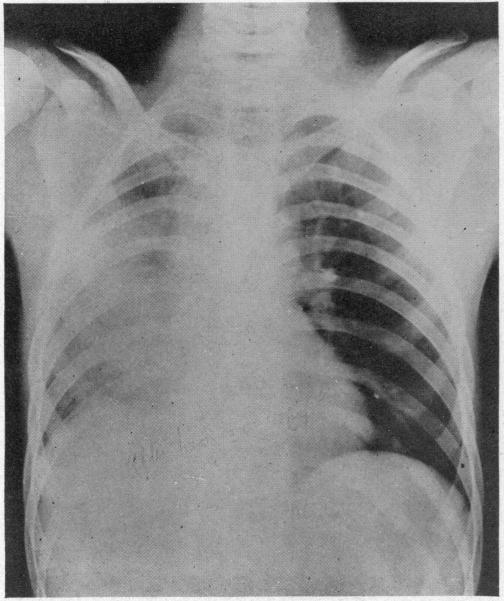

ACUTE MASSIVE COLLAPSE OF THE LUNGS: A DISCUSSION OF ITS MECHANISM AND OF ITS RELATION TO FOREIGN BODIES IN THE BRONCHI AND POST-OPERATIVE COMPLICATIONS.

Ann Surg. 1925 Sep;82(3):364-89. doi: 10.1097/00000658-192509010-00005.